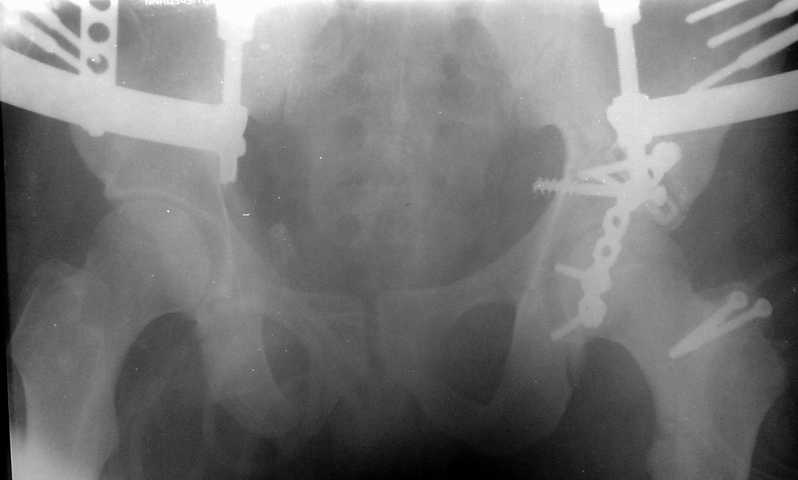

Сегодня на приеме был пациент, чьи начальный снимок напомнил обсуждаемый сейчас (см. выше). Снимки в других проекциях, показывающие истинный характер повреждения, ниже. Это inlet проекция (вход в таз) и запирательная проекция Judet.

Травма 17 ноября 2002 г., поступил к нам 1 декабря, оперирован 8-го - открытая репозиция, остеосинтез пластинками и винтами. Учитывая повреждение переднего полукольца справа, и крестца и крестцово-подвздошного сочленения слева, наложили аппарат на 2 месяца.

Для экономии места привожу интра- и послеоперационный обзорный снимок, без дополнительных проекций.